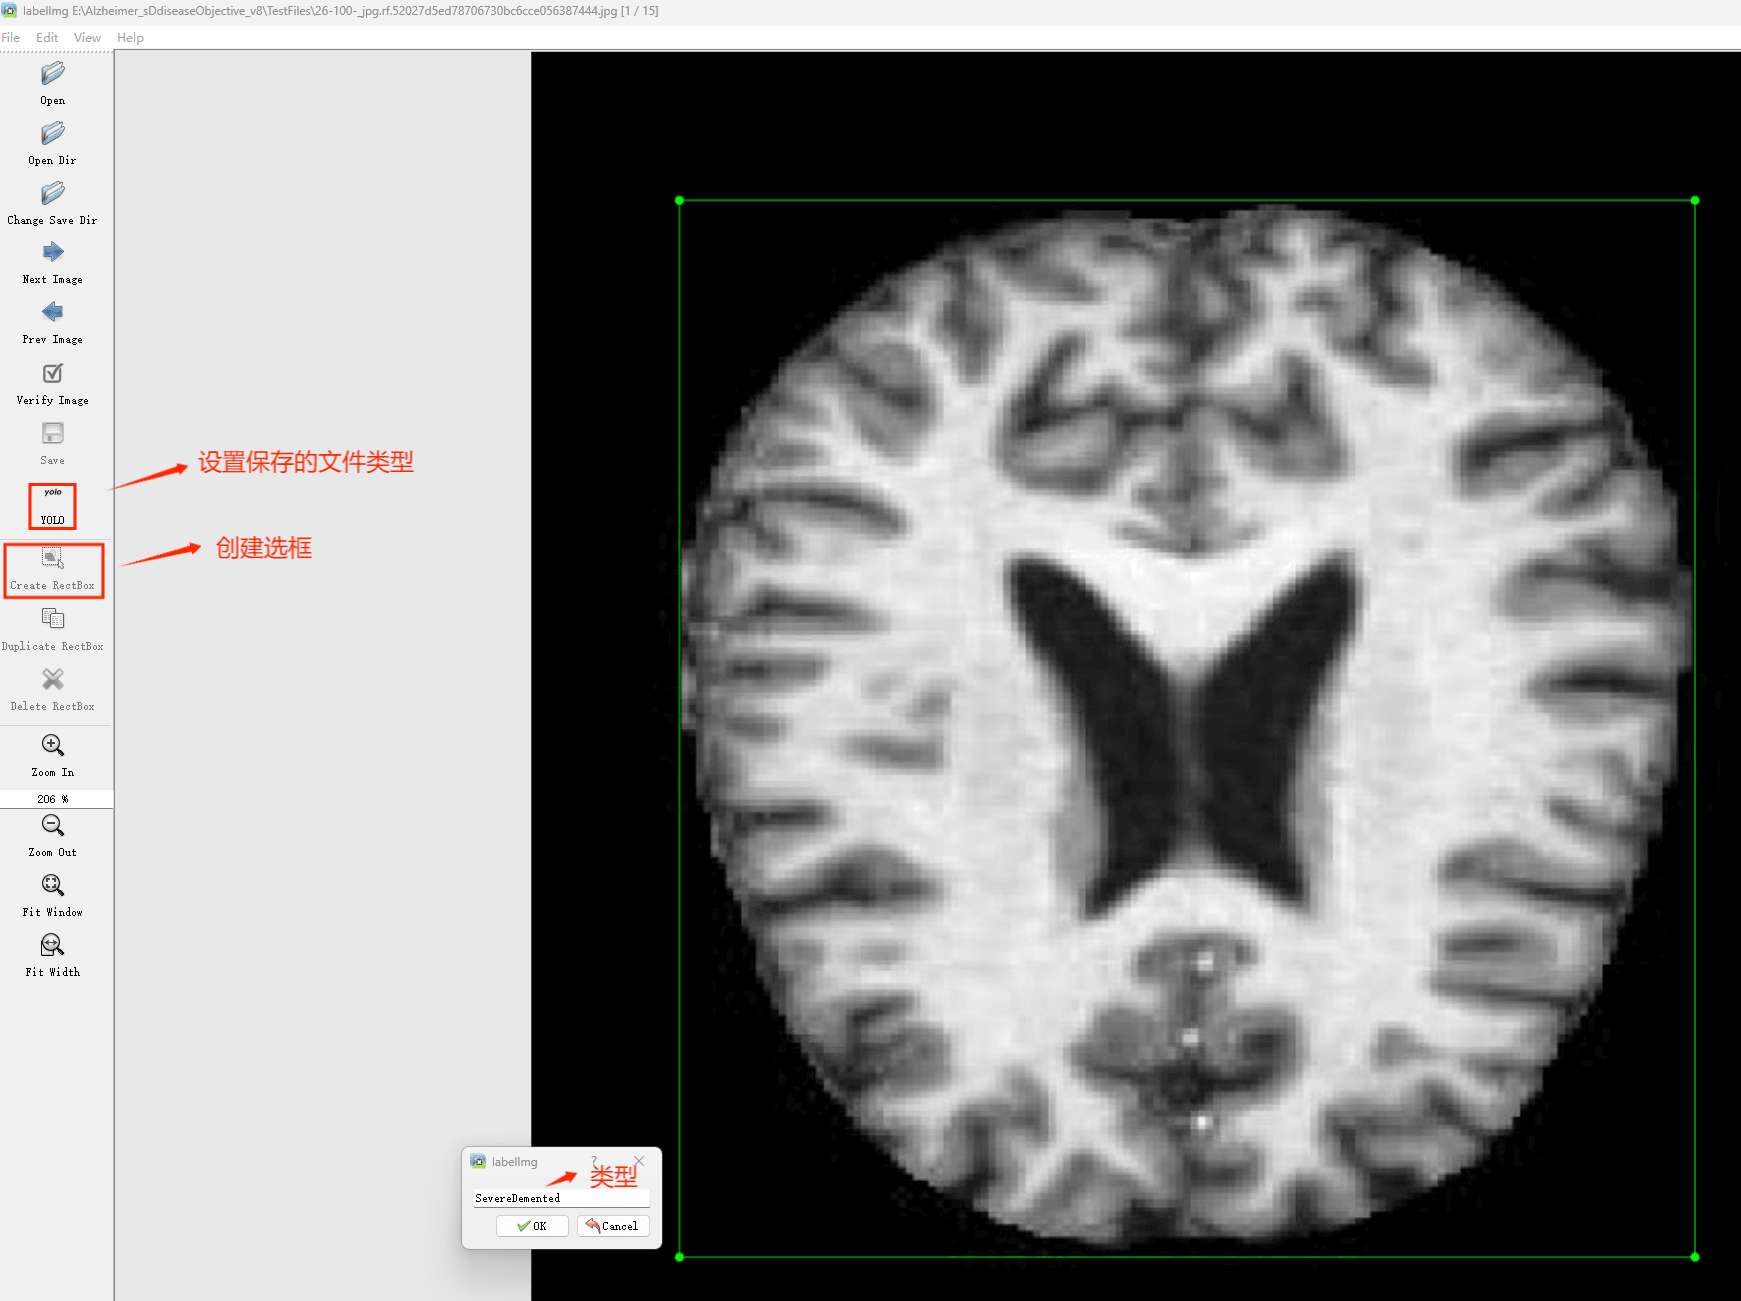

(4)YOLO模式创建标签的样式

用于存储标签信息的文件名与图片名称一致,并包含N行且每行5个数据。其中每条记录代表一个待标记的目标物体,并从左至右依次为:类ID(C)表示被标记的目标类型;Xc和Yc分别表示标注框在图像中的中心点位置;W和H分别表示标注框在图像中的宽度和高度比例。

注意:这里的中心点坐标、宽和高都是相对数据!!!

本研究采用了涵盖多种老年痴呆症相关图像的数据集,并借助Labelimg标注工具对每张图像中的目标边界框(Bounding Box)及其类别进行了精确标注。随后主要基于YOLOv8n模型构建了训练框架,在完成模型训练后对验证集的表现进行了全面分析和对比研究。整个模型开发流程包括:数据准备、模型构建与训练、性能评估三个阶段。具体而言,在本次研究中所涉及的目标分类仅限于老年痴呆症这一类别,在数据集中共有3288张图片参与其中,其中用于训练的数据占2572张,在验证集中选取了716张图片进行测试分析。如图所示的部分图片展示了典型的老年痴呆症相关图像样本

部分标注如下图所示: